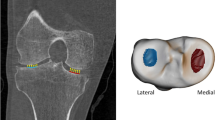

Altogether six three-dimensional volumes of interest (VOI) were automatically extracted from the medial and lateral compartments of the tibia (Fig. 1). Medial and lateral tibial spines were located by searching the highest and the second-highest coordinates along the vertical axis of the segmented sagittal slices. Because the positioning of the knee was similar among all scans, the medial and lateral compartments were identified using the tibial spines and outer borders of the tibia as landmarks. Medial and lateral subchondral bone VOIs were placed immediately below the cartilage-bone interface. The bottom coordinates for the abovementioned VOIs were defined as 10 mm below the cartilage-bone interface on the middle point of each compartment. Medial and lateral mid-part VOIs were placed under the subchondral bone VOIs. Medial and lateral trabecular bone VOIs were placed under the middle region VOIs. The height of the mid-part and trabecular bone VOIs was 10 mm. It should be noted that despite referring the VOIs to as the subchondral bone, mid-part, and trabecular bone VOIs, different bone types are mixed in the VOIs [29, 30].